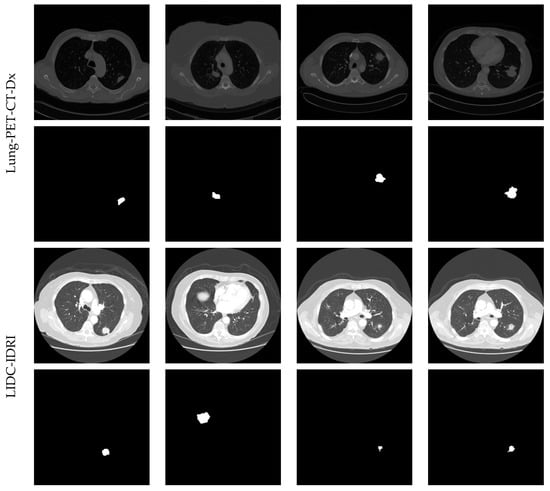

3.1. Image Database Preparation